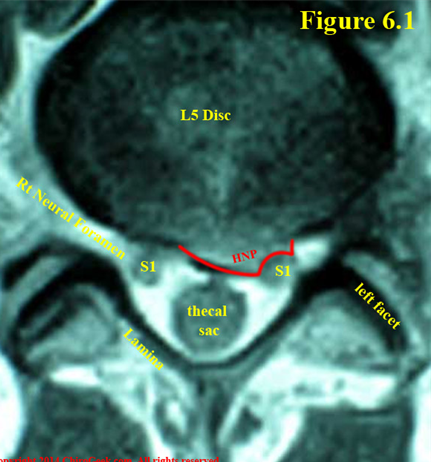

Hình 5. Lát cắt axial trên phim MRI qua đĩa đệm bình thường (A) và

thoát vị đĩa đệm L5-S1 trái (B)